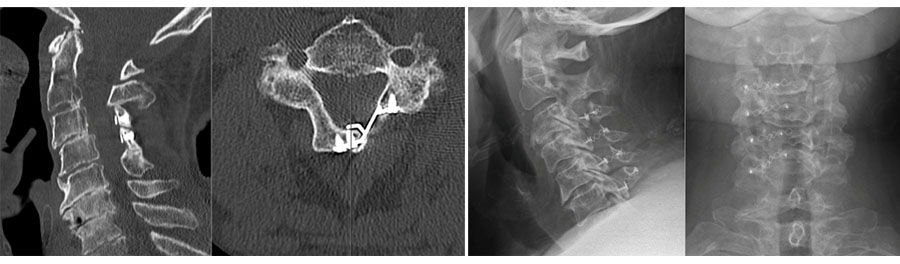

Open door posterior cervical laminoplasty. An important motion preserving surgical option for the management of DCM. Reproduced With Permission From Grochulla F., Laminoplasty. In: Vieweg U and Grochulla F. Editors. Manual of Spine Surgery. Second Edition. Springer-Verlag GmbH Germany 2023.

Recent interest has shifted toward motion-preserving surgical techniques, including cervical disc arthroplasty (CDA), endoscopic cervical spine surgery, laminectomy without fusion, and laminoplasty. Yet, evidence and best practices for these techniques in the context of DCM remain underexplored.